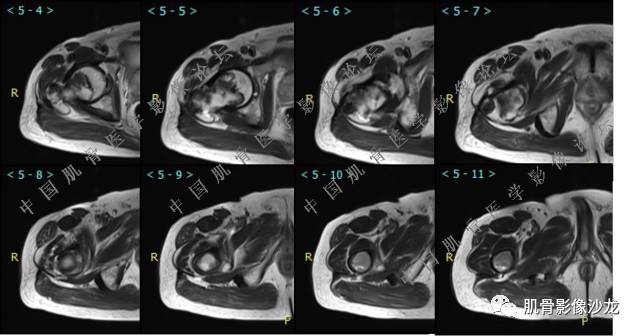

主诉:右髋及右膝部疼痛3月余

现病史:3月前打球时自觉右大腿肌肉拉伤后右髋及右膝部疼痛,自服“活血化瘀”类药物(具体不详)后自觉疼痛缓解,2月前打球时再次扭伤,右髋及右膝部疼痛明显,行走时疼痛加重,自服药物治疗,效果不佳,遂来诊。

张小林 20:08 感染类病变不支持

夏威夷的风 20:09 考虑恶性肿瘤性病变 MFH 骨肉瘤

葛英霖 20:10 判断恶性程度需要看骨髓内浸润的是肿瘤还是水肿 ,从目前看,骨肉瘤是要考虑的

张小林 20:13 磁共振有双低信号,结合CT确实要考虑有纤维成份。

医影在线 20:13 干骺端溶骨性破坏,边缘模糊,低密度肿块,似有钙化

Echo 20:13 有骨质破坏,边界不清,有软组织肿块,我觉得恶性是要考虑的

葛英霖 20:14 中间型到恶性, 需要判断是水肿还是浸润

张小林 20:23 富含巨细胞骨肉瘤?

Echo 20:23 我个人觉得,17岁男性,病灶发生在原干骺端区域,溶骨性骨质破坏,似有肿瘤骨,有软组织肿块形成,从常见病发生率来说,骨肉瘤还是要考虑的

葛英霖 20:24 这个部位有一个需要鉴别的就是软骨母

葛英霖 20:26 可以发生在干骺端